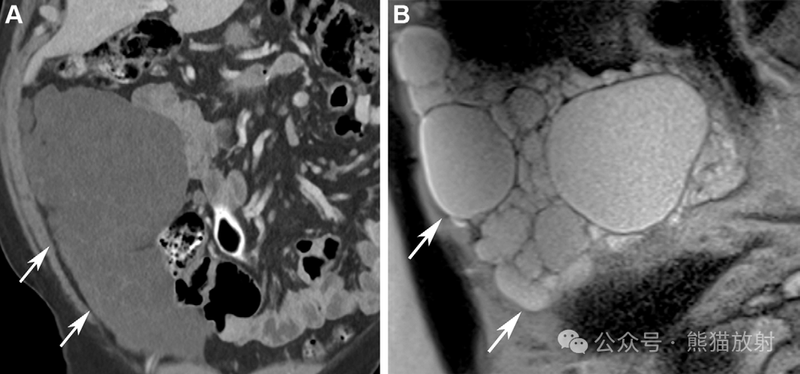

多房腹膜包涵囊肿两例。(A) 显微照片显示多个囊肿内衬单层扁平间皮细胞,具有温和的细胞核(箭头)和间皮细胞的钉状变(箭头)。周围组织无受侵。(HE×5)  (B-E) 36岁女性,多房腹膜包涵囊肿 ,有乙状结肠手术史。冠状对比增强CT (B) 和盆腔轴位T2WI (C)、冠状T2WI (D) 和对比增强(E) MR图像显示较大的多房囊性病变(箭),可见几个强化的分隔。沿着乙状结肠可见吻合器(图B箭头) 。正常的左侧卵巢(C和D中的箭头)被病变夹住,病变具有典型的蜘蛛网外观。